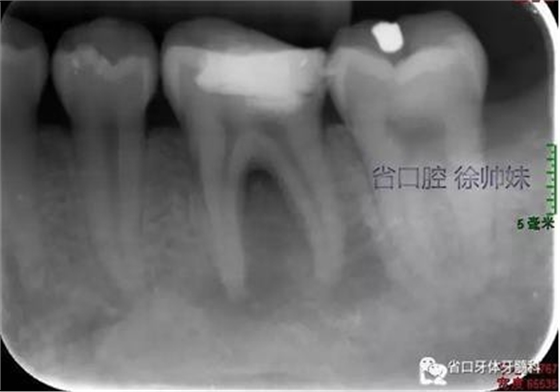

現(xiàn)病史:6個月前左下后牙區(qū)牙齦腫脹,反復溢膿,無明顯其他不適。4月前于我院牙體牙髓科(圖1)就診,診斷為“36牙周牙髓聯(lián)合病變”,建議試行36根管治療+牙周治療保留患牙,患者當時未行治療。現(xiàn)再次來我院牙體牙髓科要求進一步診治。

圖1 術前4月的根尖片